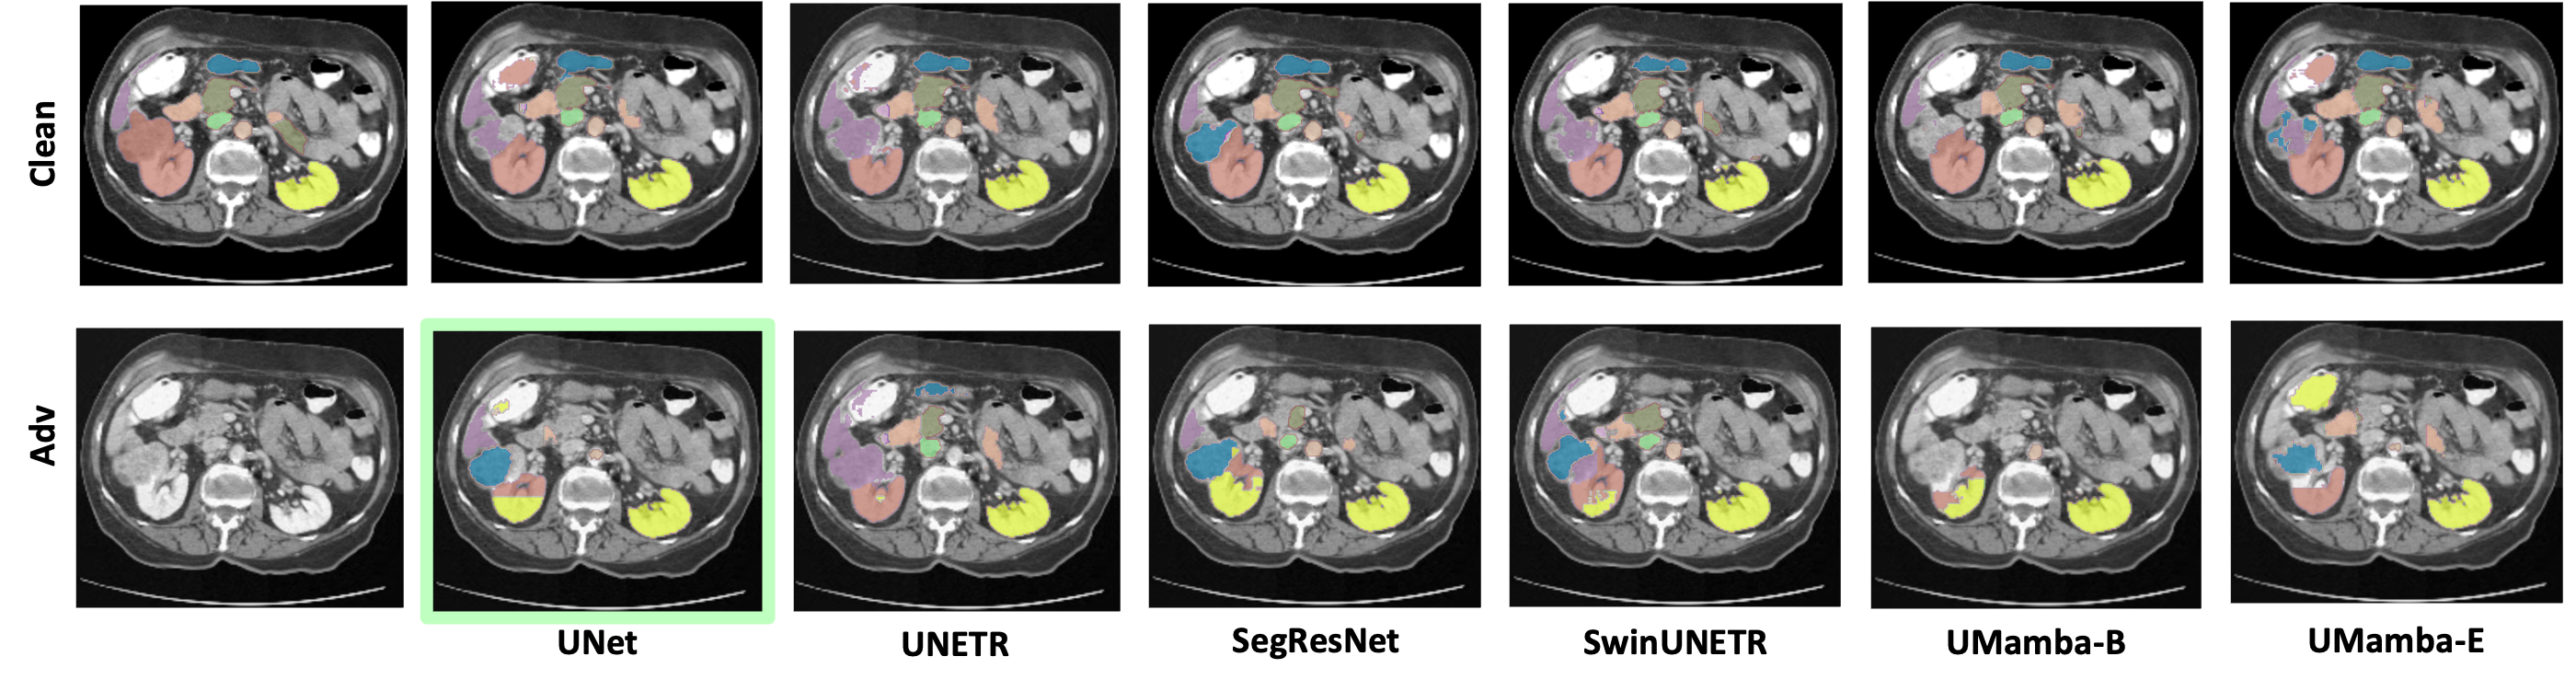

To evaluate the effectiveness of surrogate models in crafting transferable adversarial examples, we report the average attack success rate across the target models. We observe that SwinUNETR surrogate models tend to craft the most transferable adversarial examples, achieving the highest average ASR-D of , , and on BTCV, Abdomen-CT, and Hecktor datasets, respectively. However, on ACDC, it achieves a score of , slightly lower than the obtained by SegResNet. This effectiveness of SwinUNETR as a surrogate model can be attributed to its hybrid design, incorporating attributes of both CNN and transformer architectures, which contribute to the generalizability of adversarial examples across different architectures. Furthermore, upon averaging the ASR-D achieved by target models on the most transferable adversarial examples crafted by each surrogate model, we observe that the transformer-based model UNETR tend to be more robust. Similar to our white box analysis, UNETR achieves the lowest average ASR-D of , , on BTCV, Abdomen-CT, and Hecktor, respectively. However, on ACDC, SegResNet with a score of is more robust. Furthermore, consistent with Table 1, we note that Mamba-based models generally exhibit greater vulnerability to transfer-based attacks compared to their counterparts. In Figure 2, we show a qualitative comparison of transfer-based black box attack. Detailed analysis of black box setting is in Appendix F.

In Figure 7, adversarial example using VAFA is crafted on UNet model trained on Abdomen-CT dataset. Segmentation prediction of all the volumetric segmentation models is shown for the clean sample and the adversarial one. We can clearly observe that the adversarial example causes the predictions to change across all models.